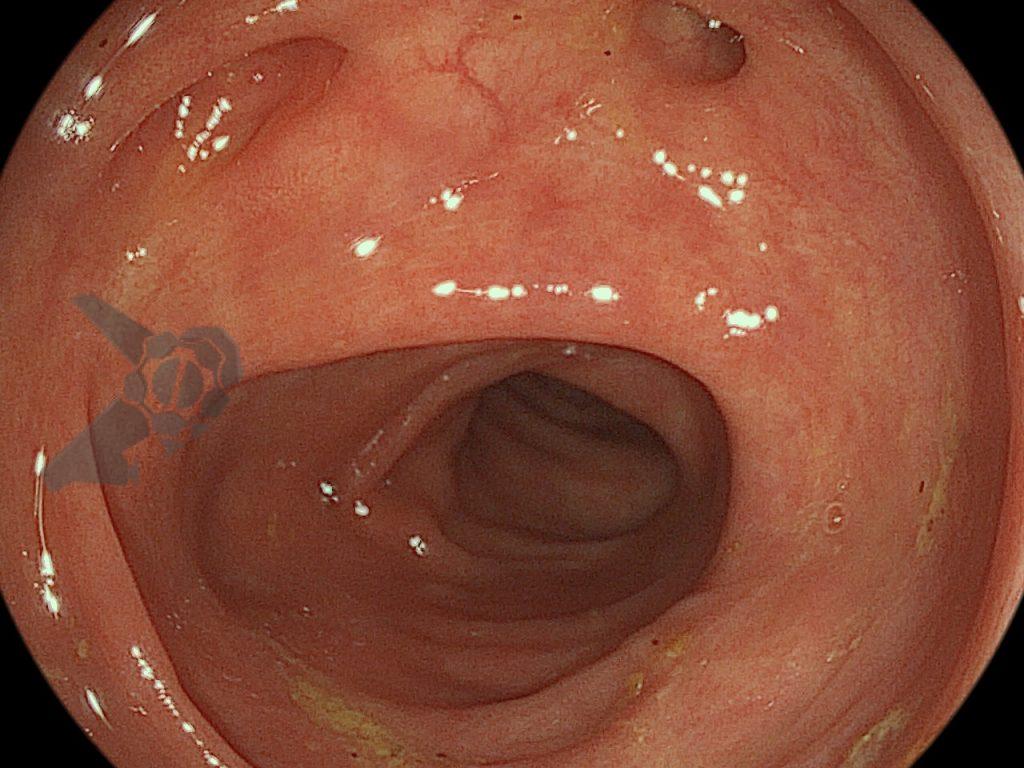

Após preparo colônico com manitol e a realização de uma nova radiografia, que não apontou qualquer mudança na posição inicial da prótese dentária desde a admissão, o paciente foi submetido a colonoscopia. Até a intubação cecal o corpo estranho não foi encontrado, com presença de doença diverticular no hemicólon esquerdo (foto 2 e 3).

Percorridos cerca de 15 cm do íleo distal, a prótese dentária foi localizada. Com o auxílio de uma alça multifilamentar, foi possível mobilizá-la e, em seguida, capturar o corpo estranho impactado, trazendo-o até o ceco (vídeo 1). A remoção cuidadosa através dos cólons foi realizada com insuflação máxima e manobras delicadas nas angulações até a extração por via retal. Durante todo o procedimento, utilizou-se CO2 como gás insuflador e foi administrado antiespasmódico (escopolamina). Na revisão pós-remoção, não havia laceração da mucosa ou sinais de perfuração nos segmentos avaliados.